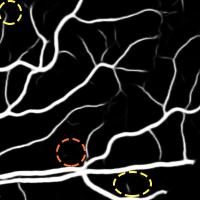

4.2 Validation of the Stationary Wavelet Transform

Having analyzed our Base System, we evaluate the effects of incorporating the SWT into it. The results of each variant are shown in Table 4, while the probabilistic predictions can be seen in Fig. 5. The patches coming from the SWT were concatenated in the input, by varying the total number of input channels. We resorted only to detail coefficients since the goal was to enhance image transitions. We started by concatenating the detail coefficients of the first level in the initial green channel input – BS + . Then, we added those of the second level – BS + + . Finally, only the latter were kept – BS + .

Analyzing the results of the tests performed, we notice that all the alternative strategies improved the performance of the Base System, in terms of Acc and AUC. This means that the use of features based on the wavelet decomposition, whose effectiveness for vessel segmentation is well-known (Soares et al.,, 2006; Zhang et al.,, 2017), is also beneficial when combined with a deep learning methodology. In particular, we see that the first level SWT coefficients used on BS + were less effective than those of the second level applied on BS + . The first level translates spectral information of higher frequencies; this seems to have induced more false positives, as can be seen in Fig. 5. On the other hand, the second level SWT coefficients introduced statistically significant differences to the Base System, in both Acc and AUC, which seems to reinforce the idea that even deep learning methods can benefit from domain knowledge. In fact, they allowed to reduce the combination of false positives and false negatives as we can see in Fig. 5 as well. From now on, we will refer to the best model (BS + ) as Proposed.